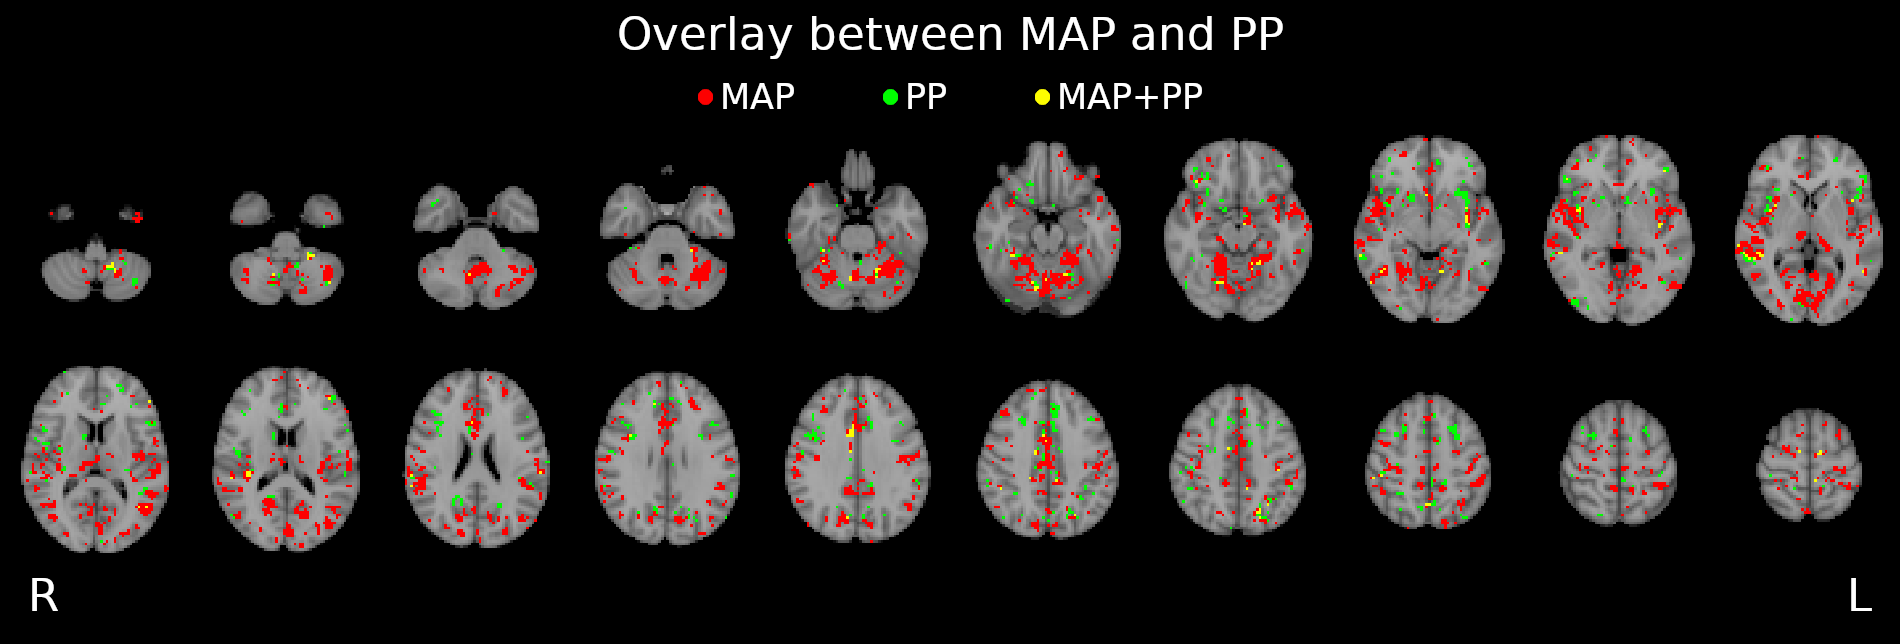

CVR and blood pressure

Due to its nature as homeostatic and cerebrovascular process, CVR is modulated by systemic changes in blood pressure¹

1. Fierstra et al. 2013 (J. Physiol.); 2. e.g. Hetzel et al. 1999 (Stroke)

Previous studies with Transcranial Doppler Ultrasound suggest to take into account blood pressure when measuring CVR²

To our knowledge, the impact of blood pressure on BOLD-fMRI based CVR estimation has not been assessed yet

We averaged the two measurements and computed the Mean Arterial Pressure (MAP) and the Pulse Pressure (PP):

Methods: effect of pressure

We used 3dLMEr¹ to set up the following LME models:

Results were thresholded at \(p<0.05\) after controlling for false discovery rate²

1. Chen et al. 2013 (Neuroimage); 2. Benjamini et al. 2006 (Biometrika)

*maps were smoothed 5mm FWHM

Methods: effect of pressure

We smooth CVR and lag maps using a dilated GM mask (white mask below) and a FWHM of 5mm (voxel size 2.5 isometric) before running 3dLMEr.

Results: blood pressure

Results: blood pressure

Results: blood pressure

Both MAP and PP should be taken into account in CVR experiments, especially in comparisons between subjects or between regions!

- Stationary blood pressure changes, expressed as MAP and PP, as well as sex, impact regional CVR estimation differently across sessions and subjects

-

Dynamic blood pressure changes are expected to impact CVR estimation, hence continuous blood pressure recordings are required to assess the matter